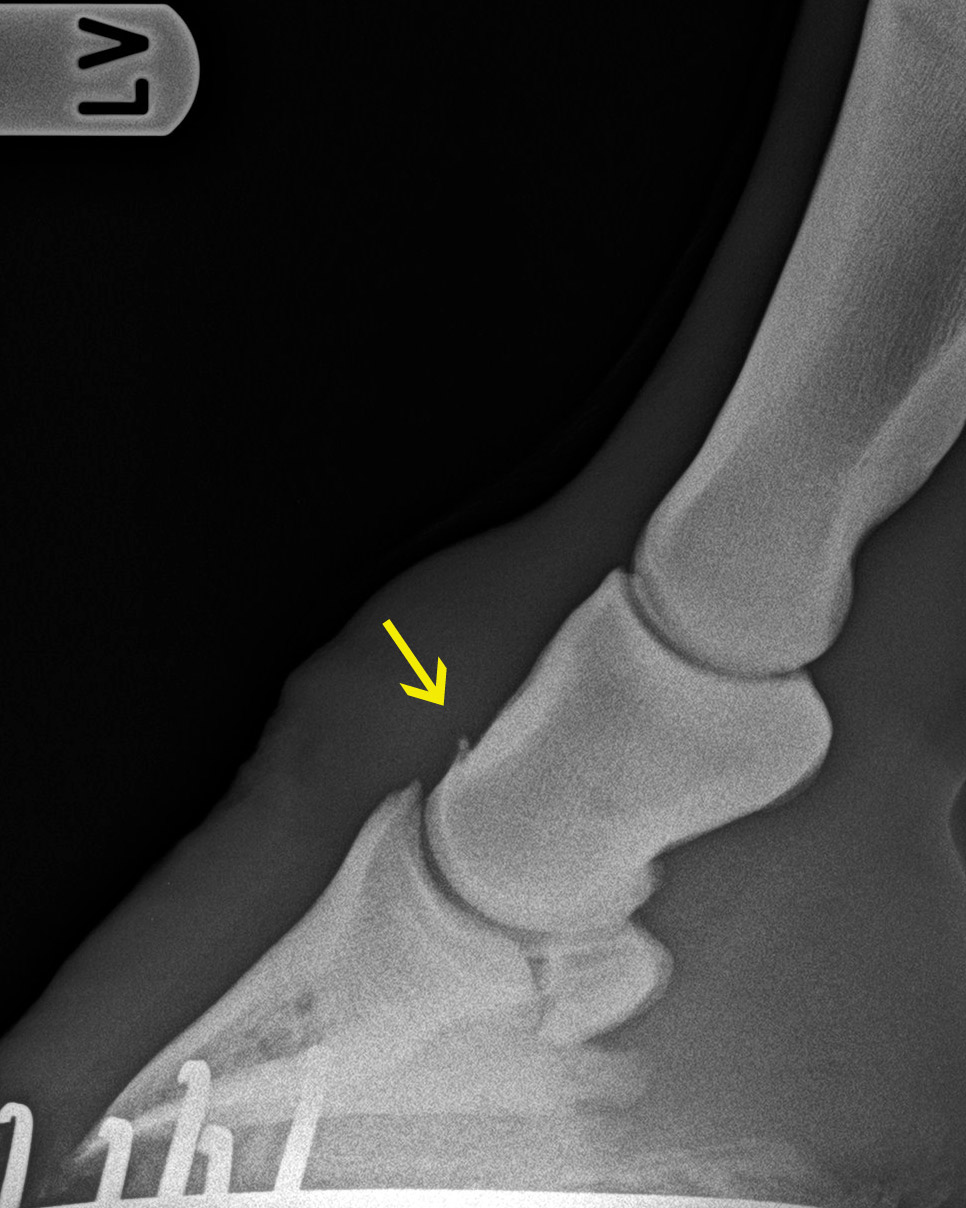

Verknöcherung am Ansatz der Hufgelenkskapsel (gelber Pfeil)